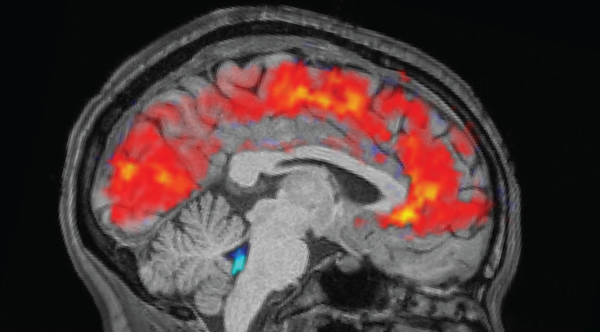

Нове дослідження на мишах, можливо, виявило механізм, що пов'язує стрес із випадінням волосся. (Зображення: Satjawat Boontanataweepol via Getty Images)